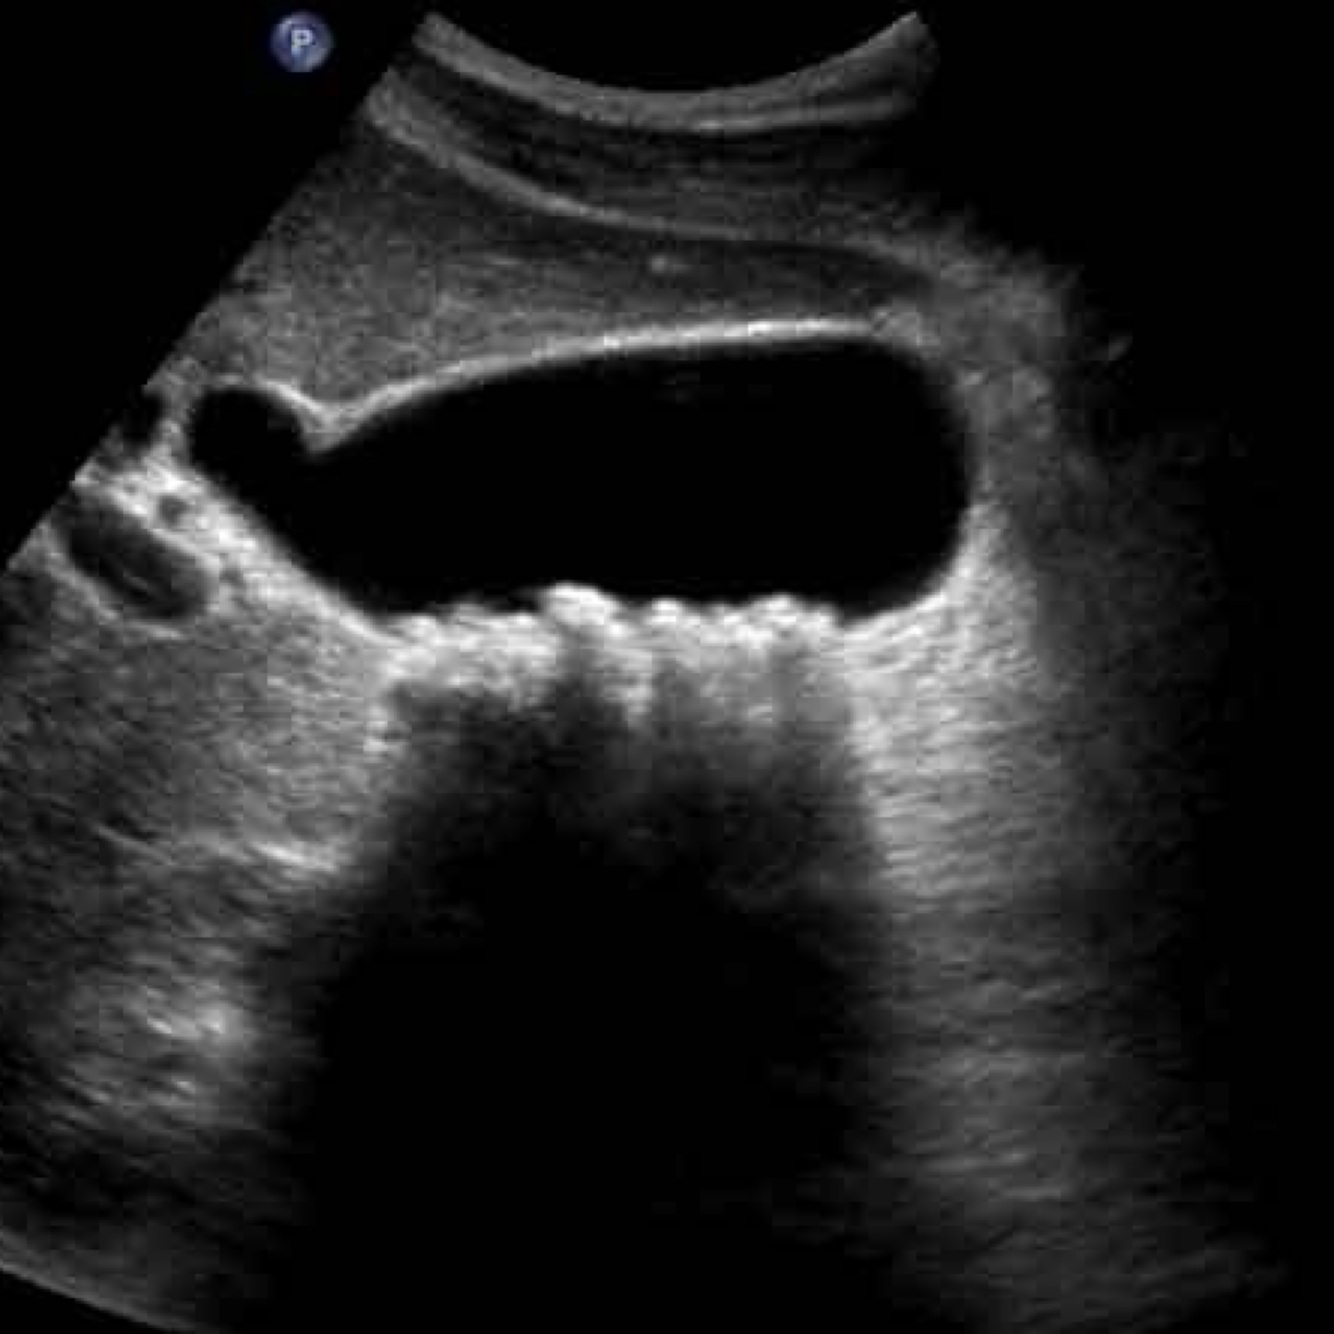

18

Q

A

GB sludge

How well did you know this?

17

May be caused by conditions

●Prolonged fasting

●Total parenteral nutrition (TPN)

●Bile stasis

●Pregnancy

●Rapid weight loss

●Recent surgery

Biliary sludge